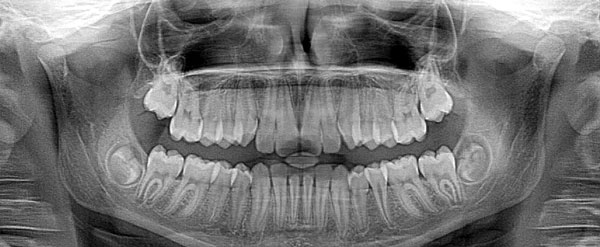

Moyens de Diagnostic :

Pour un diagnostic précis et adapté, nous disposons de plusieurs outils complémentaires.